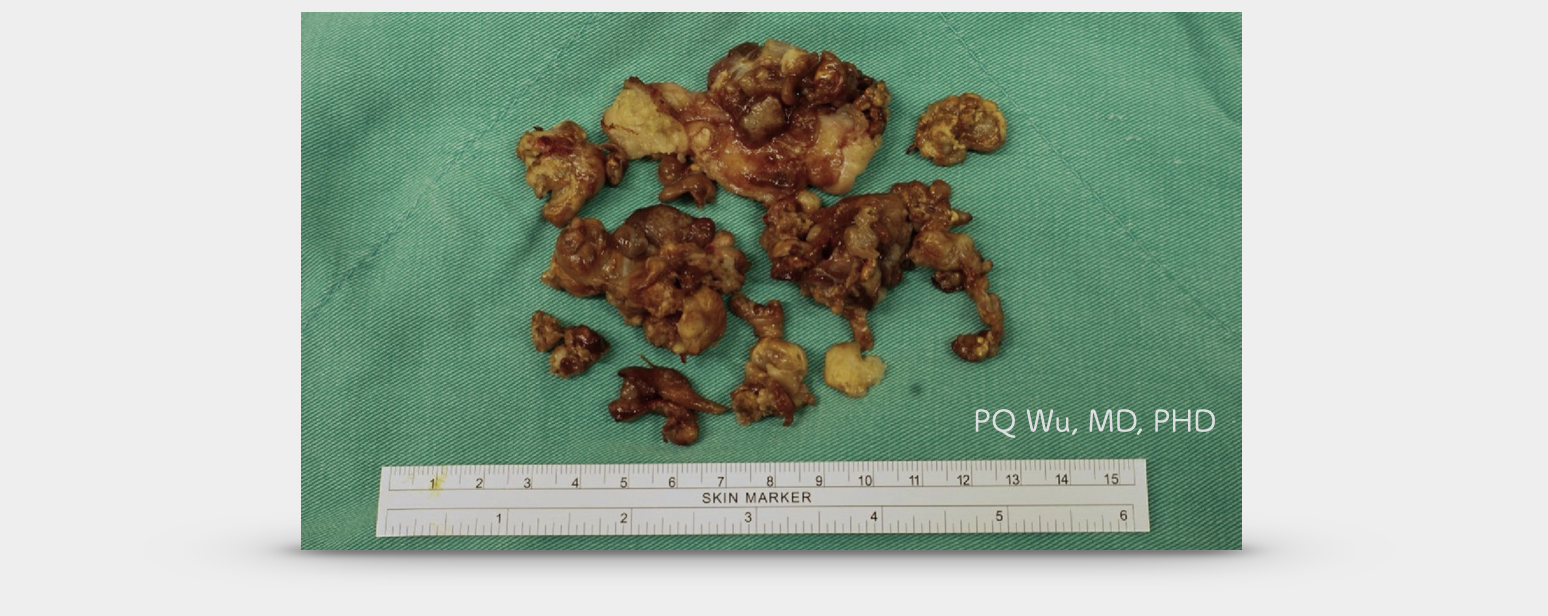

腱鞘巨細胞瘤為帶著血色、咖啡色的纖維型態,部分地方比較摸起來較為扎實,部分地方則是軟軟的結構。

38歲男性,右膝色素絨毛結節性滑囊炎